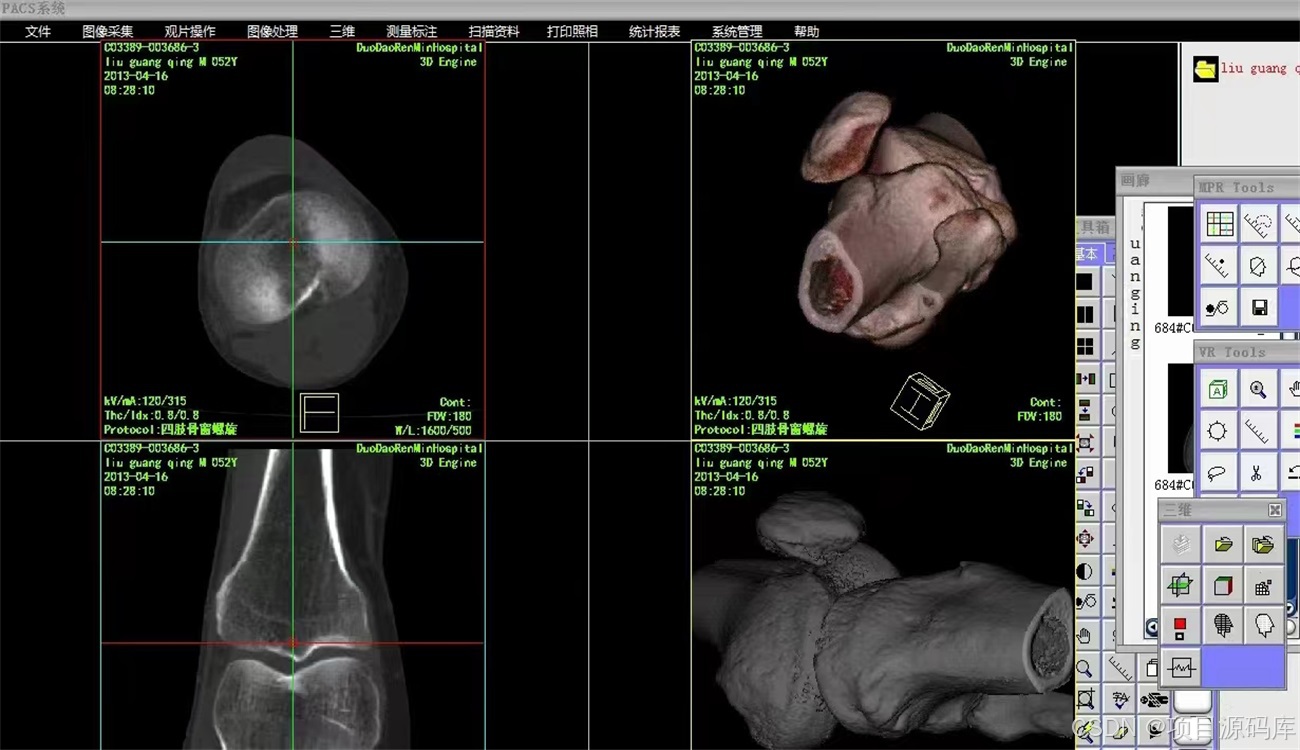

前端与可视化:Web技术 (Vue/React)、医学影像渲染引擎 (Cornerstone.js/VTK.js)、原生技术 (C++/Qt);直接面向医生的“门面”,决定了阅片诊断的效率和体验。

影像渲染引擎:这是Web PACS的技术核心。需要掌握专业的医学影像渲染库,如 Cornerstone.js (用于2D影像渲染和处理)和 VTK.js (用于MPR、VR等三维重建)。

传统C/S架构:部分对性能要求极高的诊断工作站可能仍会采用原生技术,如 C++ 结合 Qt 或 C# 的 WPF,以充分利用硬件资源 。